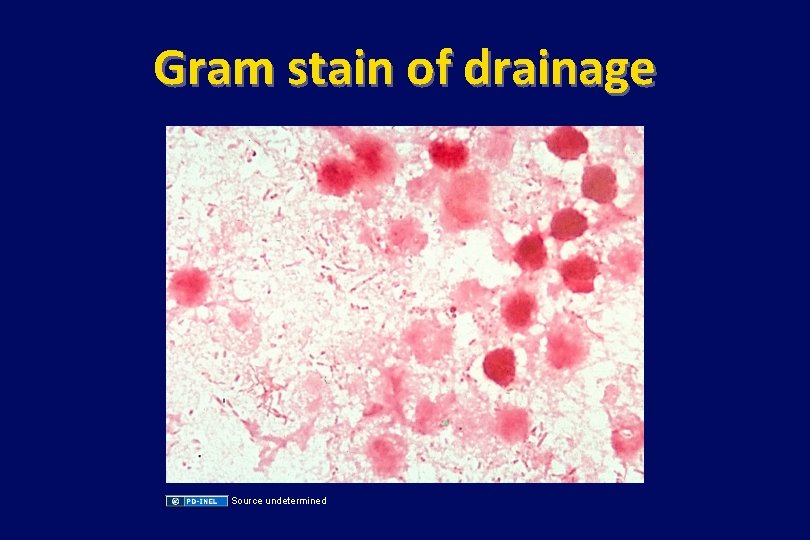

Case (continued) • The abscess is drained, and cultures of pus from the drainage grow Bacteroides fragilis. • She is treated with ampicillin-sulbactam for 14 more days. Her drain is pulled after 7 days, and she has an uneventful recovery.

Gram stain of drainage Source undetermined